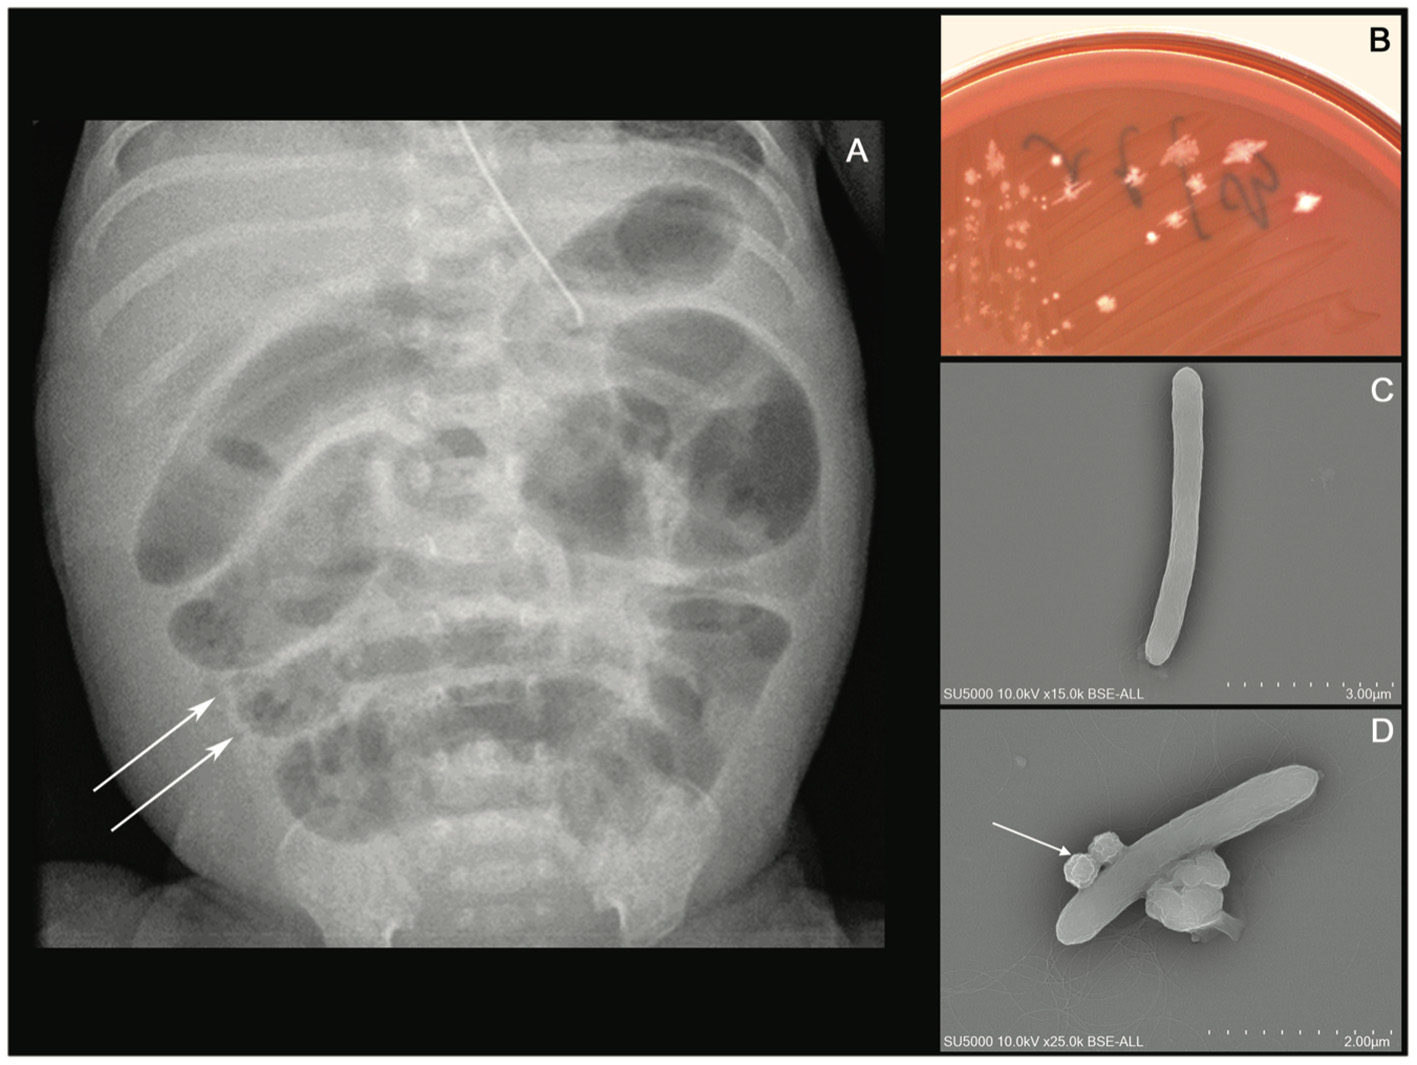

A 24+4-week-old gestational age female infant, with a birth weight of 800 g (95th percentile), was diagnosed with severe necrotizing enterocolitis (NEC) at the day of life (DoL) 21. She was born after cesarean delivery for preterm premature rupture of membranes and after antenatally completing a course of betamethasone. She was immediately admitted to our neonatal intensive care unit (NICU) and required exogenous surfactant combined with nasal continuous positive airway pressure for respiratory distress syndrome. The initial intravenous antibiotics (ampicillin and gentamycin) administered for suspected neonatal infection were stopped on DoL 2. Own breastfeeding was started from DoL1 (colostrum) and was well tolerated. On DoL 21, clinical signs of feeding intolerance suddenly occurred with bilious gastric residuals, abdominal distention, and rectal bleeding. Abdominal X-ray showed pneumatosis intestinalis (Figure 1A). White blood cells count, and C-reactive protein (CRP) respectively peaked at 40 × 109 /L (normal value range: 4.5 to 11 × 109 /L) and 240 mg/L (normal value <5 mg/L). Enteral feeding was stopped and broad-spectrum antibiotics with vancomycin, cefotaxime, amikacin, and metronidazole were initiated. The yield of blood cultures allowed for the isolation of Clostridium neonatale. More specifically, 24 h after blood sampling, one anaerobic bottle out of two blood culture sets tested positive. Colony growth was observed on Columbia agar medium (Oxoid, Dardilly, France) supplemented with 5% (vol/vol) sheep blood and incubated for 24 h at 37°C in an anaerobic chamber (80%N2, 10% CO2, and 10% H2) (AES Chemunex, Bruz, France). Colonies were cream-colored and opaque after 24 h of growth (Figure 1B). By electronic microscopy using Hitachi SU5000 scanning electron microscope (Hitachi High-Tech Corporation, Tokyo, Japan), colonies were bacilli (Figure 1C). Bacterial cells were Gram-positive (not shown). Sporulation was observed after 24 h under aerobic conditions (Figure 1D). Using matrix-assisted laser desorption ionization-time of flight (MALDI-TOF) mass spectrometry Vitek MS (bioMérieux, France), the organism was identified as Clostridium spp., and this was confirmed as C. neonatale through 16S rRNA PCR and whole-genome sequencing. In brief, strain Marseille-Q4564 exhibited a 99.66% 16S rRNA sequence similarity with C.neonataleT (Accession number AF275949.1), the phylogenetically closest bacterium standing in nomenclature. Furthermore, a digital DNA–DNA hybridization revealed a maximum identity similarity of only 91%, and an OrthoANI parameter provided values of 98.89 and 98.95%, respectively, between Marseille-Q4564 and C.neonataleT (NZ_PDCJ01000001.1 and NZ_LN890312.1). Taken together, these results confirm the status of this strain belonging to the C. neonatale species (Figure 2).

Figure 1

(A) Abdominal X-ray showing intramural bowel gas also known as pneumatosis intestinalis, (B) culture growth of cream-colored colonies on COS after 24 h of incubation at 37°C in the anaerobic chamber, (C)Clostridium neonatale rod-shaped cells using Hitachi SU5000 scanning electron microscope. Scale bar and acquisition settings are shown on the original micrograph, and (D) sporulating C. neonatale cell.